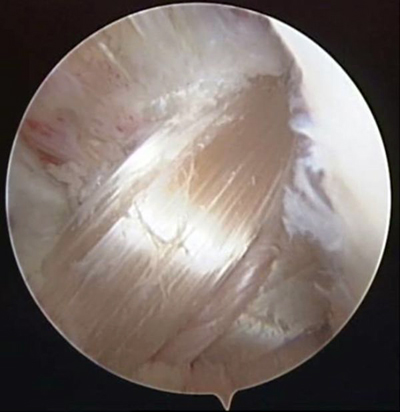

關節(jié)鏡下見重建的前交叉韌帶